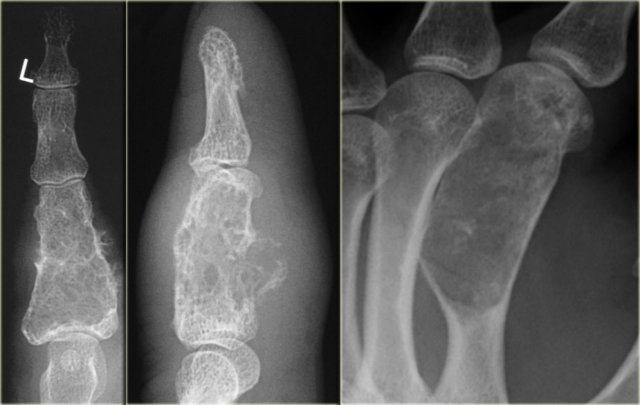

Left:

Well-defined lytic lesion with sclerotic margin and some expansion. There are fine calcifications.

This patient presented with a fracture, which is a common first presentation of an enchondroma.

Middle:

Well-defined lytic lesion without a sclerotic border also with a fracture.

Right:

Lesion with irregular cortical bone destruction. Low-grade chondrosarcoma has to be included in the differential diagnosis, but is uncommon at this specific location.